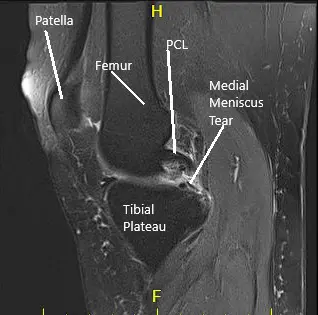

MRI of the right knee suggested medial meniscus tear and patellofemoral arthritis of the right knee.

A lateral entry portal was established, and the knee joint was examined. A peripheral tear of the medial meniscus was found. A grade 1 to grade 2 osteochondral lesion of the medial condyle of the femur was also found. The ACL had some fraying and degeneration.